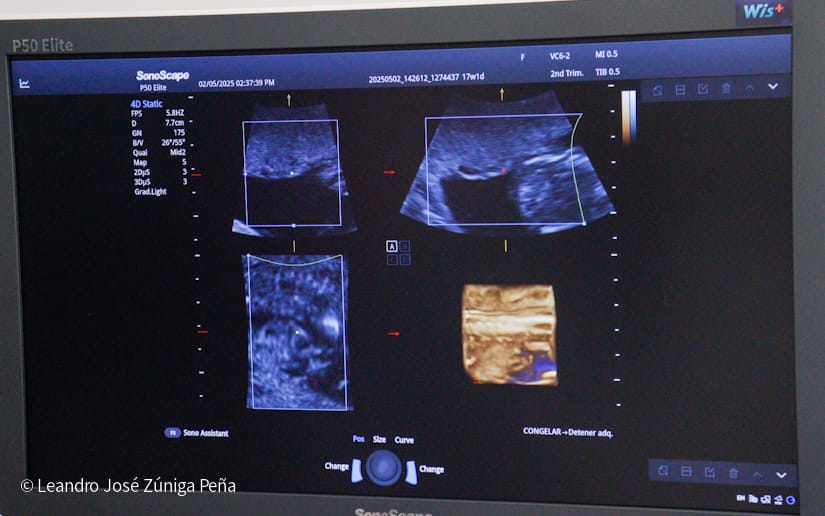

“Con estos ultrasonidos, que son de alta tecnología en el país, estamos completando 32 equipos de ultrasonido que están ubicados en las diferentes unidades de salud. Estos últimos 6 equipos nos van a permitir hacer diagnóstico de manera preventiva a la mujer embarazada, tenemos recursos humanos calificados, médicos especialistas formados por nuestro gobierno, en nuestro país, que tienen todos los conocimientos necesarios para poder hacer diagnóstico de anomalías congénitas, diagnóstico prenatal de alteraciones en la embarazada y en el feto y poder hacer prevención de la preclancia, el parto prematuro, la restricción del crecimiento fetal o bajo peso, que son morbilidades que afectan a nuestras embarazadas y a nuestro recién nacido, de igual manera, la tecnología volumétrica que se ha adquirido en estos equipos como el 3D y el 4D permite obtener mejores imágenes de anomalías congénitas para que estas pacientes que son captadas en estas unidades puedan ser referidas al Bertha Calderón”, explicó el especialista.